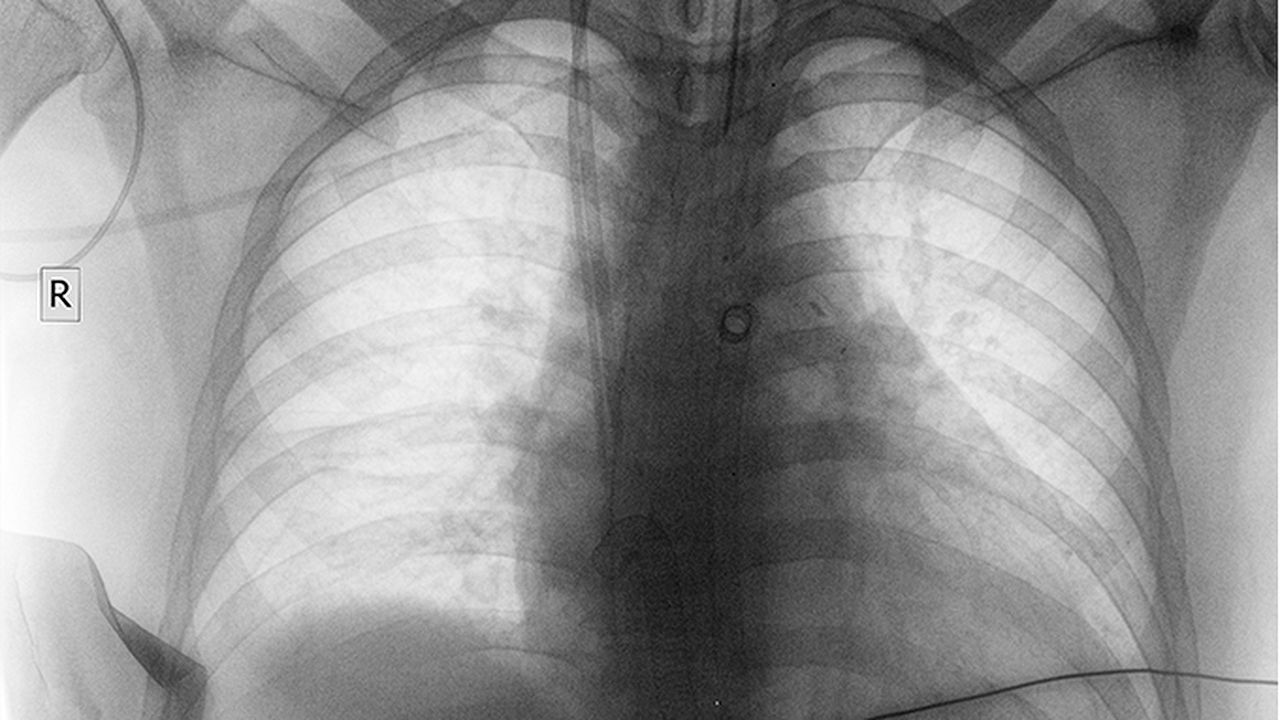

肺癌晚期患者通常需要多学科综合治疗,包括化疗、靶向治疗、免疫治疗等。选择合适的医院对提高生存质量和延长生存期至关重要。